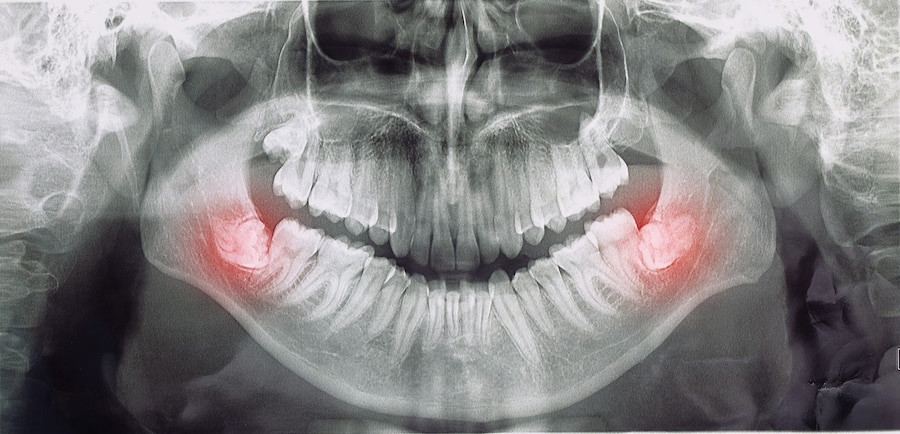

TAG: impaksi gigi

Ada 6 Artikel yang mempunyai tag "Impaksi Gigi"